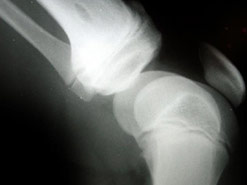

Osteoporosis

One in two women and one in five men in the UK over the age of 50 will break a bone because of osteoporosis.

Losing bone density is a natural part of the ageing process but what makes some people more susceptible to porous bones than others?

Being post-menopausal, taking certain prescription drugs, smoking and drinking are all risk factors for developing osteoporosis.

In this week’s Check Up Barbara Myers is joined by Dr Nicola Peel, consultant in metabolic bone medicine to take your questions on bone health and osteoporosis.

What are the best forms of prevention, treatment, who is most at risk and how can you get yourself tested?